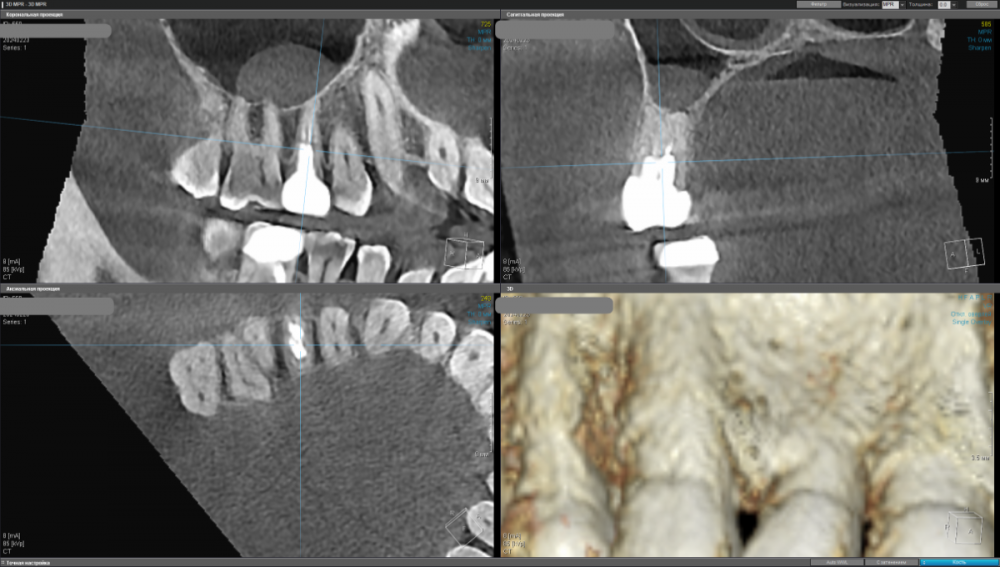

kamacho Опубликовано 24 февраля, 2024 Автор Поделиться Опубликовано 24 февраля, 2024 Попробую привлечь ваше внимание дополнительными снимками. Вопросы которые я себе задаю когда смотрю на КТ: 1) Между 14 и 15 зубом, это убыль фуркации или артефакт при съемке кт ? 2) В районе 37 ого зуба это артефакт или кариес ? Я пытаюсь санировать ротовую полость уже наверное лет пять, и никогда не удается решить проблему. Прошел множество клинник (наверное штук 5-6, включая 1 зарубежную). Но после попыток лечения, возникает одна и таже проблема, как только начинаю добавлять углеводы(не сладости) в рацион, какой-то очаг инфекции дает о себе знать. Буду очень признателен если поможете советом или догадкой. Ссылка на комментарий

Carioznik Опубликовано 25 февраля, 2024 Поделиться Опубликовано 25 февраля, 2024 15.02.2024 в 18:43, kamacho сказал: есть ли показания для лечения этого зубика? По идее есть, но нужно разбираться 15.02.2024 в 18:43, kamacho сказал: Могут ли не до конца пролеченные корни вызывать такую симптоматику ? Нет 17 часов назад, kamacho сказал: Между 14 и 15 зубом, это убыль фуркации Нет. Похоже, что на 14 есть кариес. Возможно это и причина кровоточивости и запаха. Но нужно смотреть настоящую КТ , а не скрины. 18 часов назад, kamacho сказал: районе 37 ого зуба это артефакт или кариес ? Больше на артефакт похоже, но это не точно: нужно смотреть настоящую КТ , а не скрины 1 Ссылка на комментарий